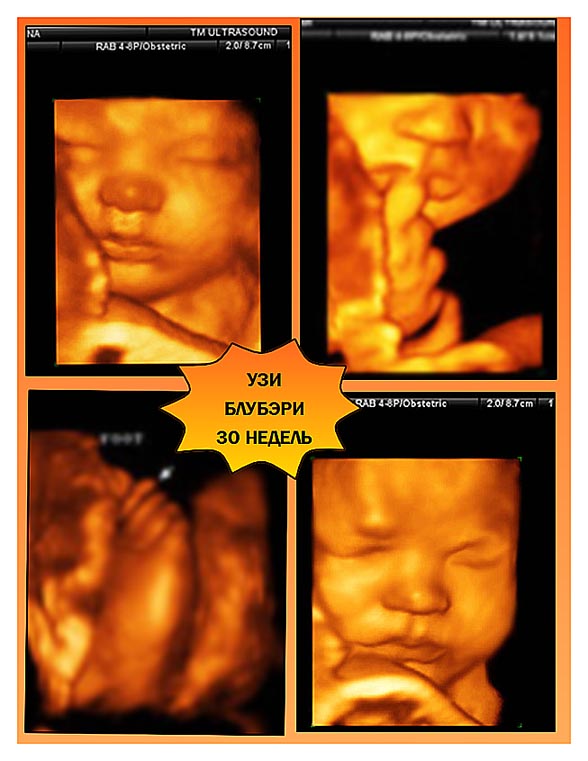

Леша. УЗИ. Внутриутробные портреты.